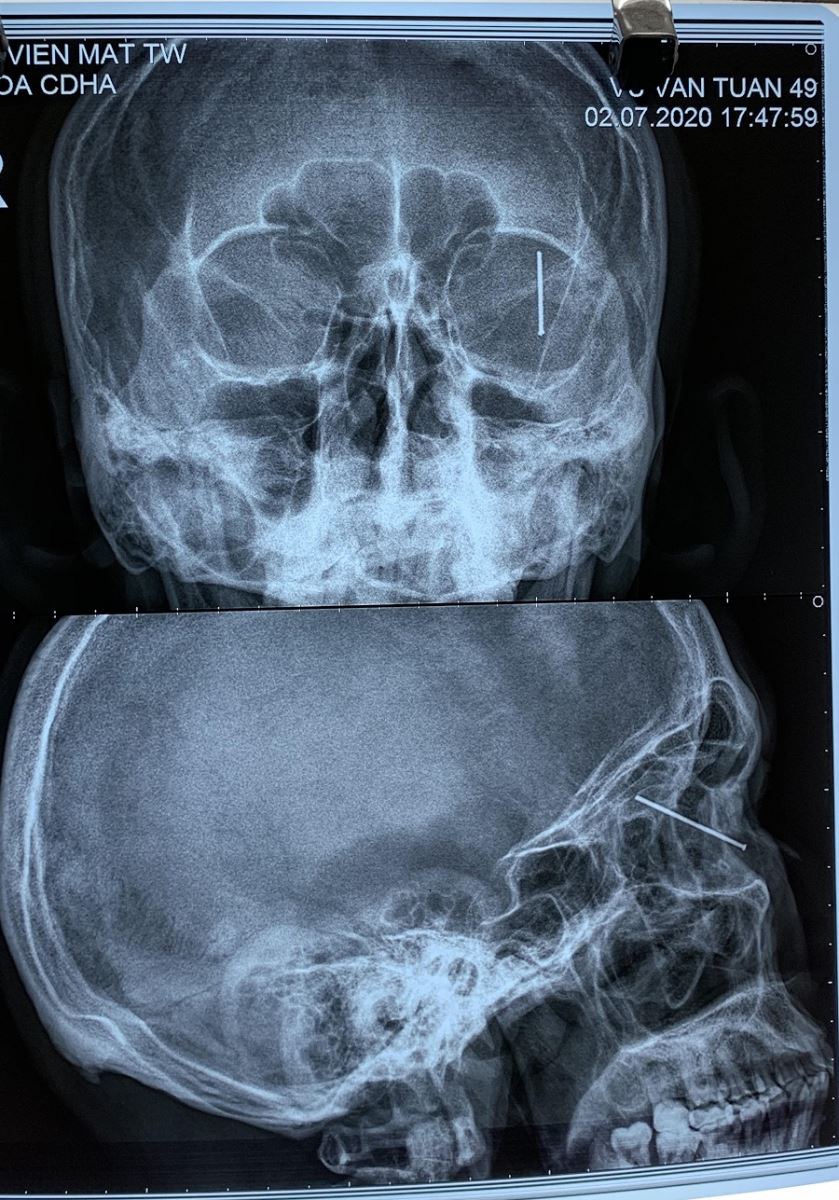

Khi chụp X-quang để đánh giá thương tổn, bác sĩ xác định cây đinh nằm trong lòng nhãn cầu, xuyên thấu nhãn cầu. Kíp trực đã tiến hành phẫu thuật lấy chiếc đinh, khâu lại giác mạc, tiêm kháng sinh nội nhãn cho bệnh nhân.

Hình ảnh chiếc đinh dài 3cm cắm sâu vào mắt bệnh nhân